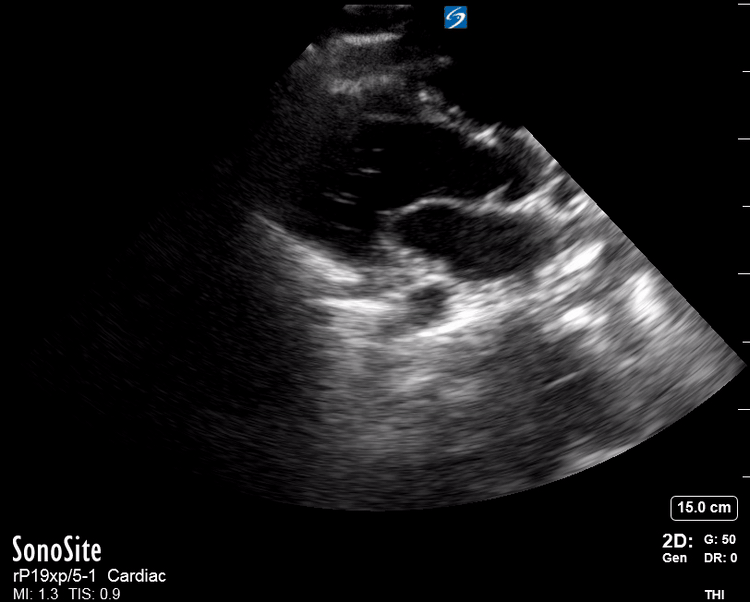

Effusion: is there a pericardial or pleural effusion?

Pericardial effusion is a continuum and can potentially evolve into haemodynamic collapse. Tamponade physiology is detectable earlier with ultrasound than with traditional physical examination, and it has been demonstrated that PoCUS improves mortality in penetrating cardiac trauma. Timely and accurate diagnosis is, therefore, vital.

THE VIEWS

The subxiphoid view is the most reliable for detecting pericardial effusion. Still, it is ideal to obtain different views not to miss a focal effusion as small amounts of fluid can lead to tamponade physiology. Tamponade does not link strictly to the size of the effusion, but correlates more with the speed of onset, causes, and haemodynamic effects.

PITFALLS & PLEURAL EFFUSIONS

A common error is to confuse a pericardial fat pad with effusion. Fatty tissue has a heterogeneous echotexture, moving in coordination with the myocardium, and it cannot be tracked around the heart, especially posteriorly and to the apex. Another pitfall is misinterpreting a pleural effusion as a pericardial effusion. However, they can be differentiated by their relationship to the descending aorta. Pericardial effusion may be seen between the aorta and the LV free wall, whereas pleural effusions are posterior to the descending aorta. Lastly, other causes, namely hypovolaemia and large pleural effusions, can cause RA and RV collapse.